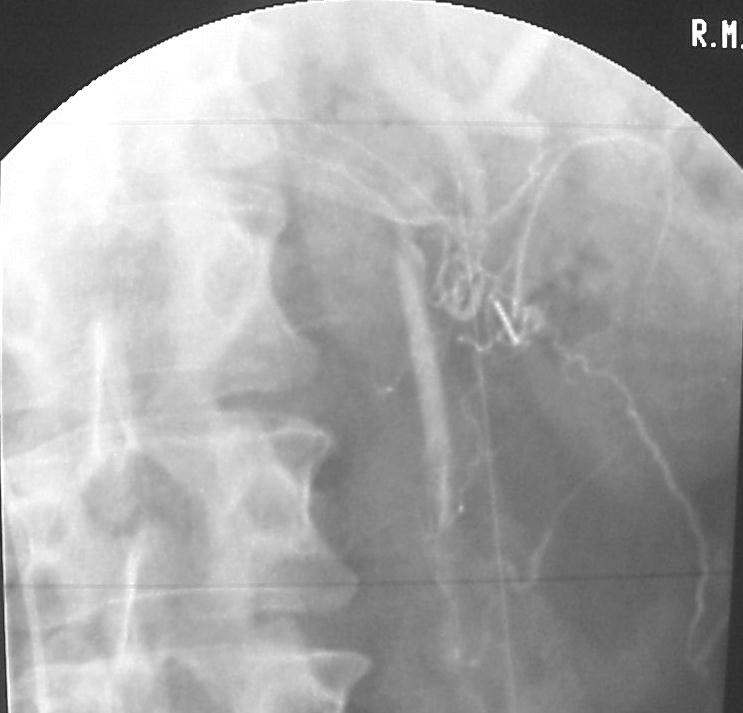

![]() 精索静脉解剖

精索静脉充盈通过肾包膜/输尿管的侧支循环

右侧精索静脉通过肾或肾包膜静脉充盈